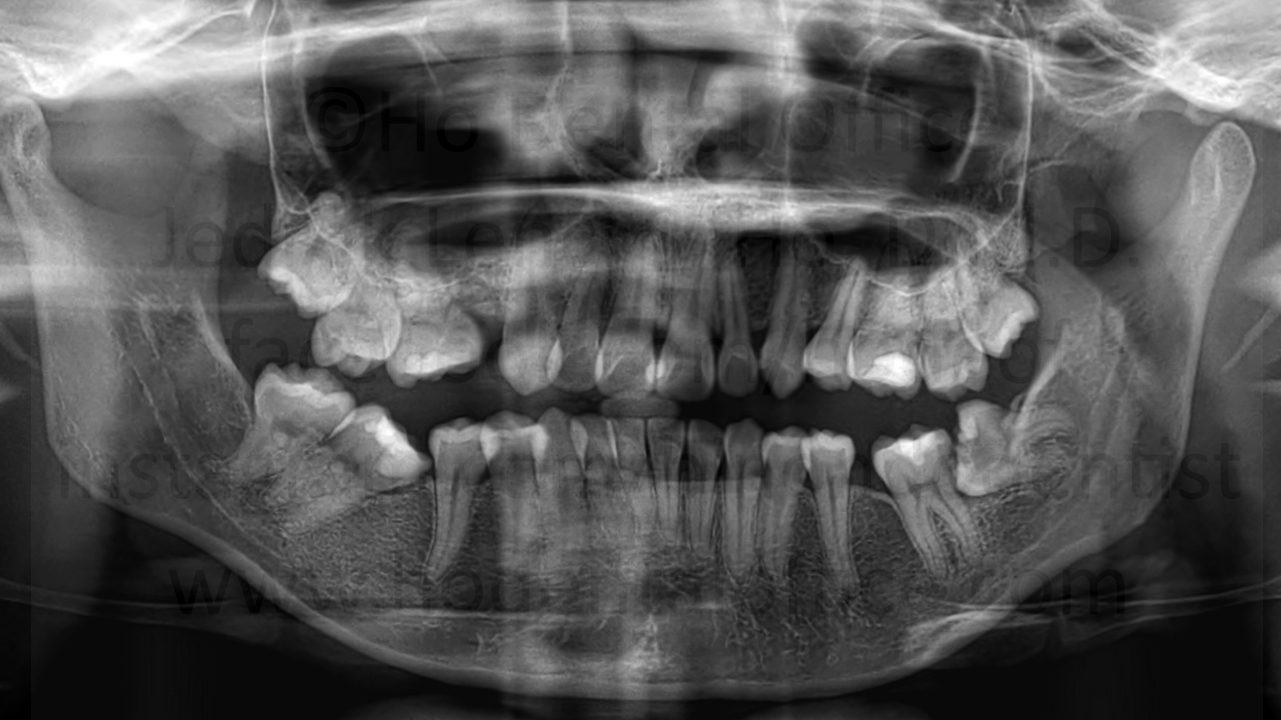

- prevention of bone loss - When impacted third molars (wisdom teeth) are taken out before they fully mature, chances are, the bone level behind the second molar will be higher. As the third molar fully matures, it also takes up more space thus resorbing more bone behind the second molar. Younger patients also have better healing than older patients, and so when the fully matured third molar is extracted from an older patient, there is a higher chance that the bone level behind the second molar is suboptimal, which may cause the second molar to be more wobbly because of poor bone support.

![]() | ![]() | ![]() |

| bone loss due to presence of third molars, note the bone level of the second molar on the side facing the third molar is already on the level of the second molar's roots | ||